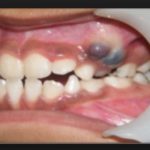

Также если родители не могут понять, почему синеют десна у детей, стоит отправиться к стоматологу. Чаще всего причины заключается в поражении мягких тканей инфекцией, которая скапливается в ранке и вызывает воспаление. Нередко младенцы тоже сталкиваются с подобной проблемой при прорезывании зубов. Синяя десна у ребенка наблюдается при травмировании тканей резцом на этапе его активного роста. Возникает подкожная гематома – сегодня эту проблему успешно лечат в любой клинике.